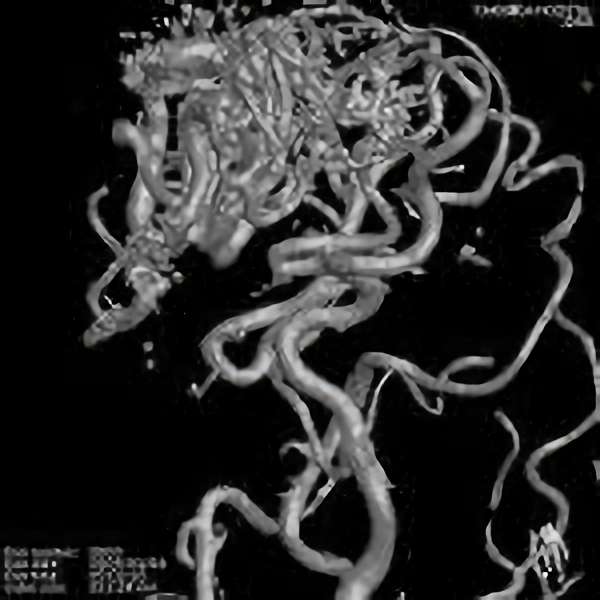

No.359 モニタリング

No.359 手術前

No.359 手術中

No.359 手術後

出血既往があり。2回の手術前血管内手術の後に、

Lateral transpeduncular approachにより再々出血予防を目的に

摘出手術を行う。完全摘出であることを確認した。

手術による合併症や後遺症なしで退院した。経過良好。